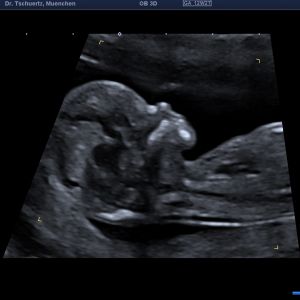

Früher Fehlbildungsultraschall / Ersttrimesterdiagnostik

Viele schwerwiegende komplexe Fehlbildungen können bereits früh erkannt werden. Ein unauffälliger Befund kann somit zu einer deutlichen Reduktion von Sorgen und Ängsten beitragen. Bei auffälligem Ultraschallbefund kann eine weiterführende Diagnostik zeitnah erfolgen.

Nackentransparenzmessung

Ziel dieser Diagnostik ist eine Wahrscheinlichkeitsberechnung für das individuelle Risiko ihres Kindes an einer Chromosomenstörung wie zum Beispiel der Trisomie 21 (Down- Syndrom) erkrankt zu sein. Dazu wird in der 11+0 bis 13+6 Schwangerschaftswoche die sogenannte Nackentransparenz (eine Flüssigkeitsansammlung unter der Haut im Nackenbereich des Kindes) gemessen. Unter Berücksichtigung des mütterlichen Alters, des Schwangerschaftsalters, der Dicke der Nackentransparenz und biochemischer Parameter (ß-HCG und PAPP-A) wird ein statistisches Risiko für das Vorliegen bestimmter Chromosomenstörungen errechnet. Sowohl falsch- positve als auch falsch- negative Vorhersagen sind möglich.